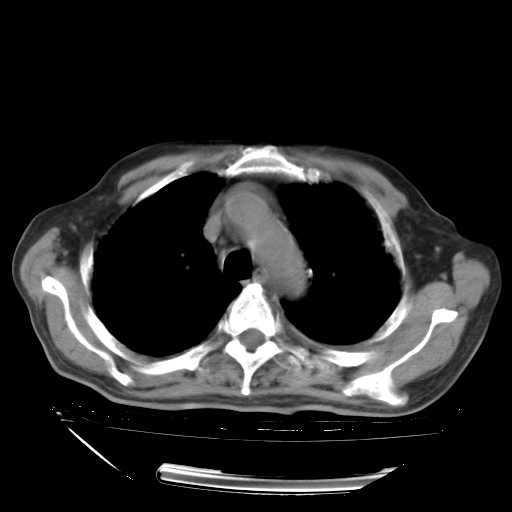

经过24天治疗,岳父的病情基本稳定。生活基本可以自理,可以下床活动。呼吸困难早已消失。体温基本正常。

只是甲强龙用80mg时血小板升到正常,改为60mg后又降到63×10*9/L。

主要治疗甲强龙80mg×14天,60mg×10天;同时抗结核(异烟肼+利福平+乙胺丁醇)。环磷酰胺0.1 tid 10天。

特别感谢胡教授、高管、桃子版主给出关键的治疗建议。桃版把所有肺部影像和全部临床资料请所在医院呼吸科、感染病科、结核科、临床免疫科专家会诊。临床免疫科专家制定了完整的治疗方案。